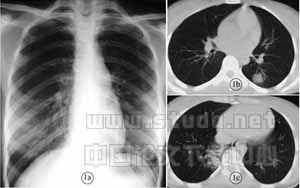

图1 女,23岁,高热7天,多次X线胸片检查未发现异常;发病第8天胸片(a),第9天胸部CT检查(b、c),在右肺内基底段及左下叶背段见斑片渗出影

本文86例SARS患者显示X线胸片异常出现的时间多在发病的4~7天(73.3%),初期最常见的表现为斑片状模糊影,单侧多(61.6%)。而有学者研究表明早期行胸部CT扫描,可使异常影像所见明显提前。因为SARS的初期病灶为孤立或散在分布的体积较小且密度极淡的渗出性病灶,胸片不易显示,再有一些病灶位于正位胸片的盲区。本组1例患者为我院护士,高热7天,多次X线胸片检查未发现异常;第9天胸部CT检查,在右肺内基底段及左下叶背段见斑片渗出影,均为平片的盲区(图1)。由于胸部CT检查敏感度远高于平片检查,对疾病的早期诊断起着重要的作用,因此早期高度疑似的病例,如有条件均应进行胸部CT扫描。